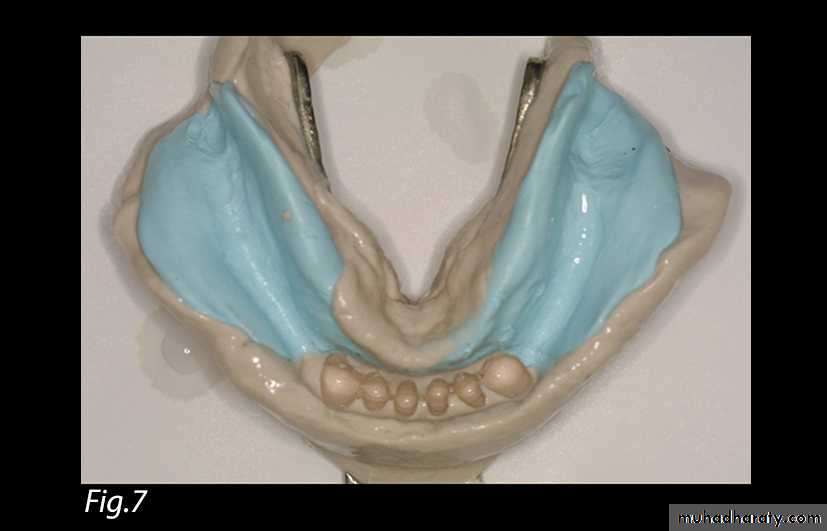

Fig. 7: Pick-up impression relating edentulous

areas to residual teeth.In this technique, the role of the compound occlusal rims is to transmit the positive pressure exerted by the fingers to the edentulous ridge areas and to ensure a functional relationship between teeth and edentulous ridges. The impression is finally poured with dental stone (Silky-Rock, Whip Mix, Louisville, KY).